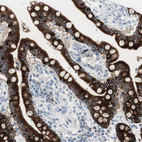

Immunohistochemistry analysis in human stomach and skeletal muscle tissues using HPA007912 antibody. Corresponding AGR2 RNA-seq data are presented for the same tissues.